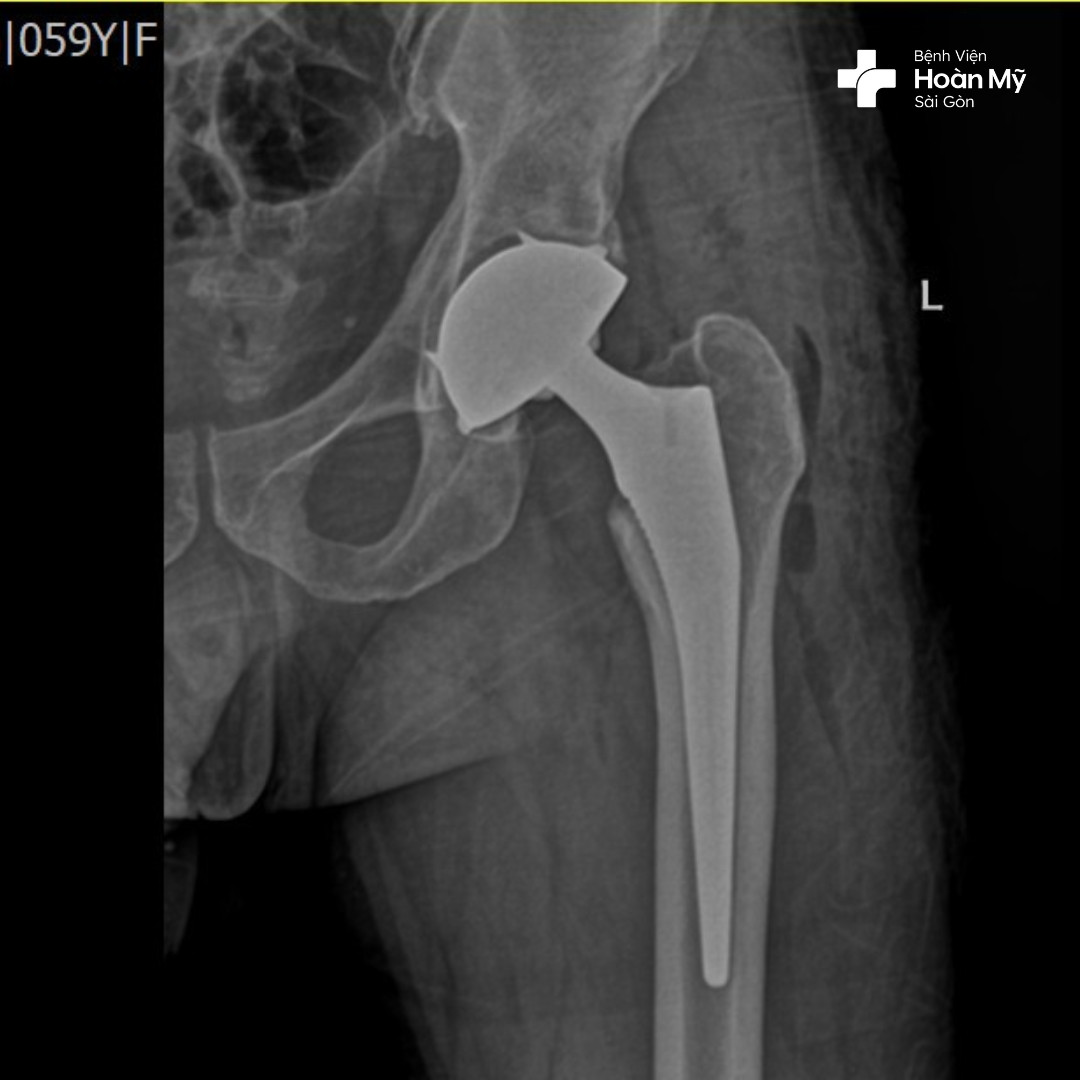

Hình ảnh X-quang trước khi phẫu thuật của người bệnh

Kỹ thuật tiên tiến này được thể hiện trong quá trình phẫu thuật thay khớp háng, bác sĩ phẫu thuật chỉnh hình tại bệnh viện Hoàn Mỹ Sài Gòn sẽ THAY THẾ cả HAI đầu khớp háng bị hư hỏng bằng các bộ phận nhân tạo cùng một lúc giúp người bệnh không phải chịu đau 2 lần, tránh được biến chứng phẫu thuật, tiết kiệm về tài chính. Đây là kỹ thuật đòi hỏi tay nghề cao của bác sĩ có nhiều năm kinh nghiệm.